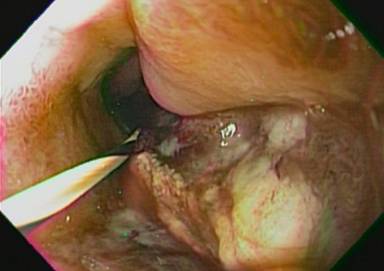

Upper endoscopy had previously shown duodenal stenosis due to circumferential ulcerated and infiltrative lesions in all cases. Facing a high probability of an unsuccessful ERCP, we discussed the possibility of endosonography-guided biliary drainage and duodenal stenting with the surgical and oncological teams. We performed the procedure following the same sequence in all cases. For the whole procedure, the patient was under general anesthesia and fluoroscopic guidance was used. A therapeutic duodenoscope (TJF-160, Olympus, Tokyo, Japan) was introduced and advanced until the duodenal bulb. A 0.035 guidewire (Jagwire®, Boston Scientific, Natick, MA, USA) was advanced through the duodenal stenosis until the proximal jejunum (Figure 1). The stenosis was dilated with a dilation balloon (CRETM Balloon Dilator, Boston Scientific, Natick, MA, USA) until 15 mm. The duodenoscope was advanced but the major ampulla could not be identified. The guidewire was left in place and the duodenoscope was removed. A linear array echoendoscope (GF UCT-140, Olympus, Tokyo, Japan; Alfa 5 processor, Aloka, Tokyo, Japan) was introduced. Endosonography examination was performed to look for the dilated common bile duct, the largest left intrahepatic duct and the presence of collateral veins. In all cases, the largest left intrahepatic ducts were smaller than 6 mm and we did not attempt the antegrade transhepatic access. The common bile duct was punctured with a 19-gauge needle (EUSN-19T, Cook Medical, Bloomington, IN, USA) (Figure 2). Bile was aspirated and contrast was injected to confirm an adequate position of the needle (Figure 3). After confirmation with fluoroscopy, a 0.035 guidewire (Jagwire®, Boston Scientific, Natick, MA, USA) was advanced through the needle into the common bile duct and the needle was retrieved. A 6-Fr cystotome (Endo Flex, Voerde, Germany) was then inserted over the guidewire to create a bilioenteric communication (Figure 4). In four patients, a partially covered biliary self-expandable metallic stent (WallFlex® 60/100 mm, Boston Scientific, Natick, MA, USA) was inserted into the common bile duct and successfully deployed, creating a choledochoduodenal fistula (Figure 5). In one patient (Patient#2), we deployed an uncovered biliary metallic stent (WallFlex® 60/100 mm, Boston Scientific, Natick, MA, USA). The echoendoscope was removed and the duodenoscope was introduced over the duodenal guidewire. A non-covered duodenal self-expandable metallic stent (WallFlex® 120/220 mm, Boston Scientific, Natick, MA, USA) was inserted over the guidewire and deployed in all patients (Figures 6 and 7).

Figure 1. Duodenal stenosis. |